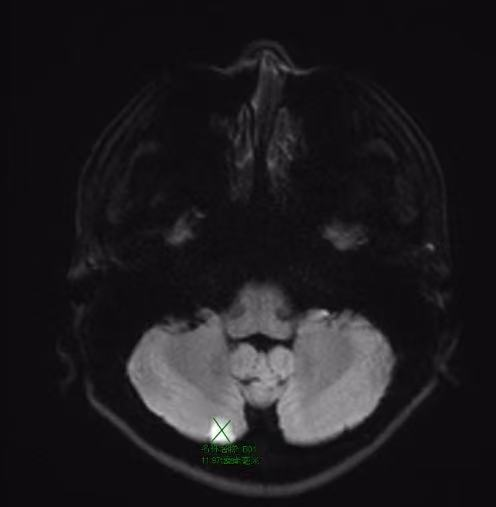

小脑梗死